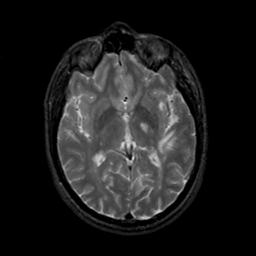

MR Study #19, August 25, 1991 -- Slice #25